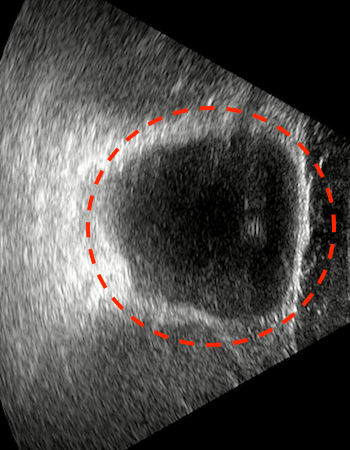

いまの幾代さんのぼう胱はこんな感じになっているかもしれません。

※正常なぼう胱 ※潰れたぼう胱